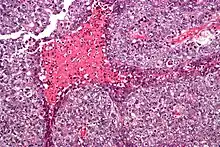

Embryonal carcinoma. H&E stain.

The gross examination usually shows a two to three centimetre pale grey, poorly defined tumour with associated haemorrhage and necrosis.[2]

The microscopic features include: indistinct cell borders, mitoses, a variable architecture (tubulopapillary, glandular, solid, embryoid bodies – ball of cells surrounded by empty space on three sides), nuclear overlap, and necrosis.